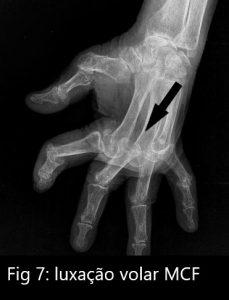

A tensão dos tendões flexores puxam F1 em sentido volar (palmar) provocando sub-luxação de F1. A sub-luxação vai agravando evoluindo para luxação completa da MCF (figura 7).